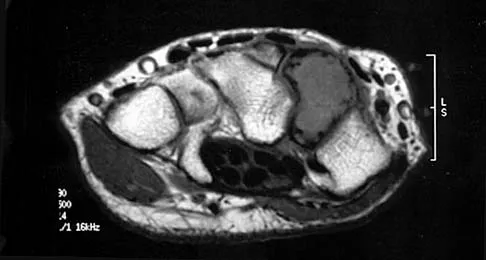

A 19-year-old girl has had pain and swelling in the right ankle for the past 4 months. She denies any history of trauma. Examination reveals a small soft-tissue mass over the anterior aspect of the ankle and slight pain with range of motion of the ankle joint. The examination is otherwise unremarkable. A radiograph and MRI scan are shown in Figures 45a and 45b, and biopsy specimens are shown in Figures 45c and 45d. What is the most likely diagnosis?